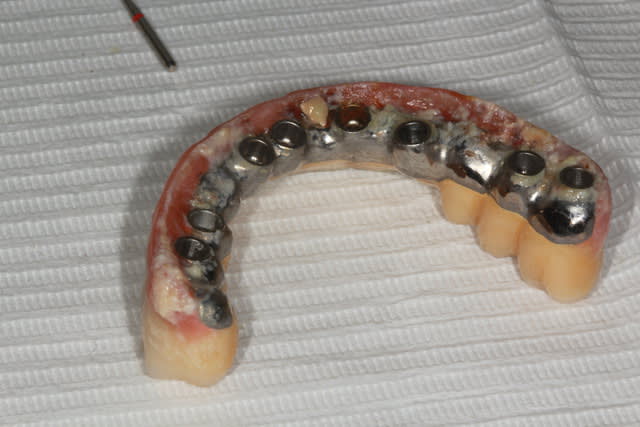

Exemple d'un bridge que j'ai repris il y a quelques mois, posé il y a 5 ans par un gars très renommé de ma région, le dentiste des stars .

Ne pas oublié qu'on apprend de ses erreurs, mais aussi de celles des autres, et que donc d'autres aprennent aussi de nos erreurs ...

Img 7908 kcbb0v - Eugenol

Img 7909 d6y5bl - Eugenol

Img 7928 jq7gn8 - Eugenol

Img 7929 eqcz7i - Eugenol